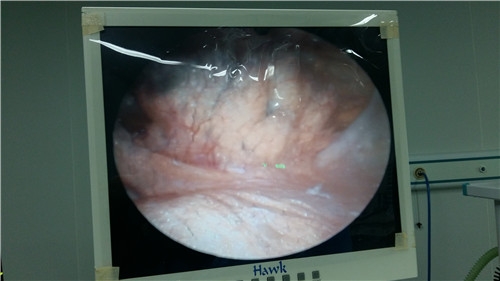

三、激光针刀的治疗过程

1、局麻后,选择适合型号的针刀进入病灶部位,松解剥离粘连,疏通经络,恢复动态平衡。

2、导入适合频率的新型激光,消炎镇痛,促进机体修复,提高免疫力,避免组织再次粘连。

3、对治疗部位进行常规护理创可贴外敷。整个治疗过程仅需30分钟,治疗后观察15-20分钟如无不适即可出院。